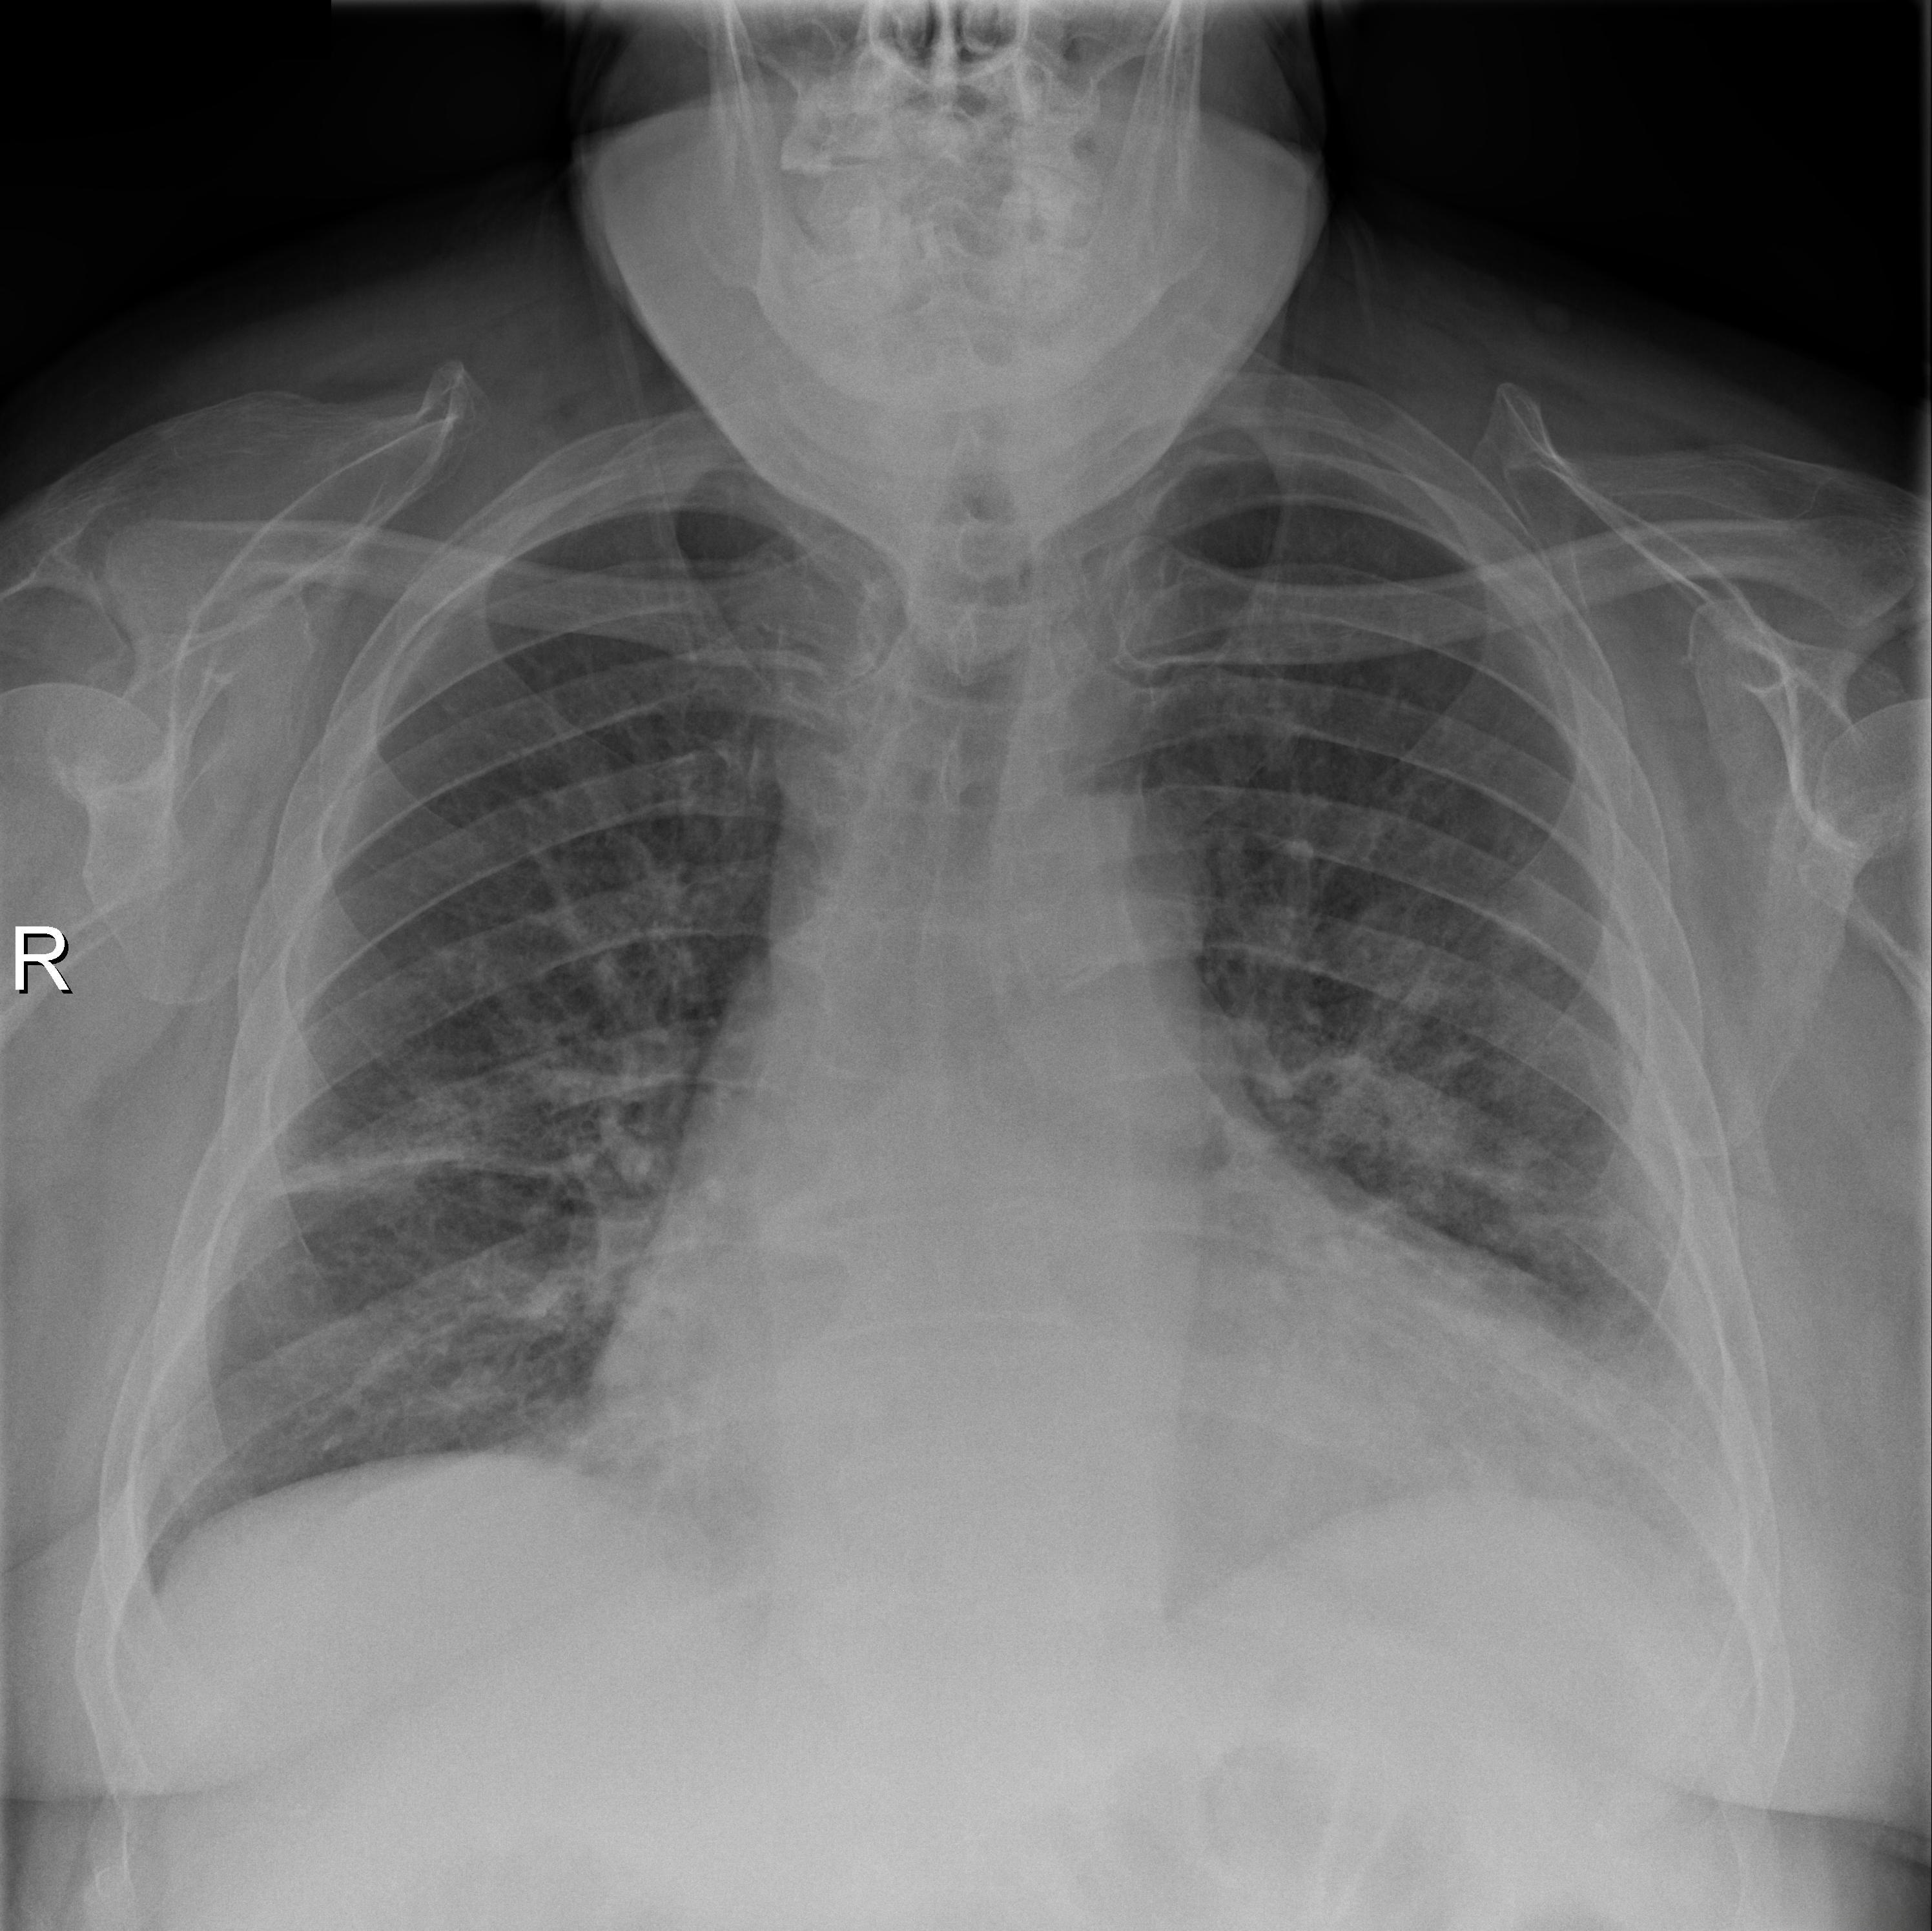

由放射学会国家联盟于2018年发起的RSNA Pneumonia Detection Challenge旨在推动自动化肺炎检测技术的进步与应用。该挑战提供了一个包含约30,000份患者胸部X光片的数据集,并对其中每张图片都进行了标注以确定是否存在肺结核情况。这些来自不同医疗中心的影像资料涵盖了多种X光成像系统与设备的应用场景

在完成处理后,并对图像进行肺炎标注的目标检测数据集中共有6012张图像被分类为病变区域。